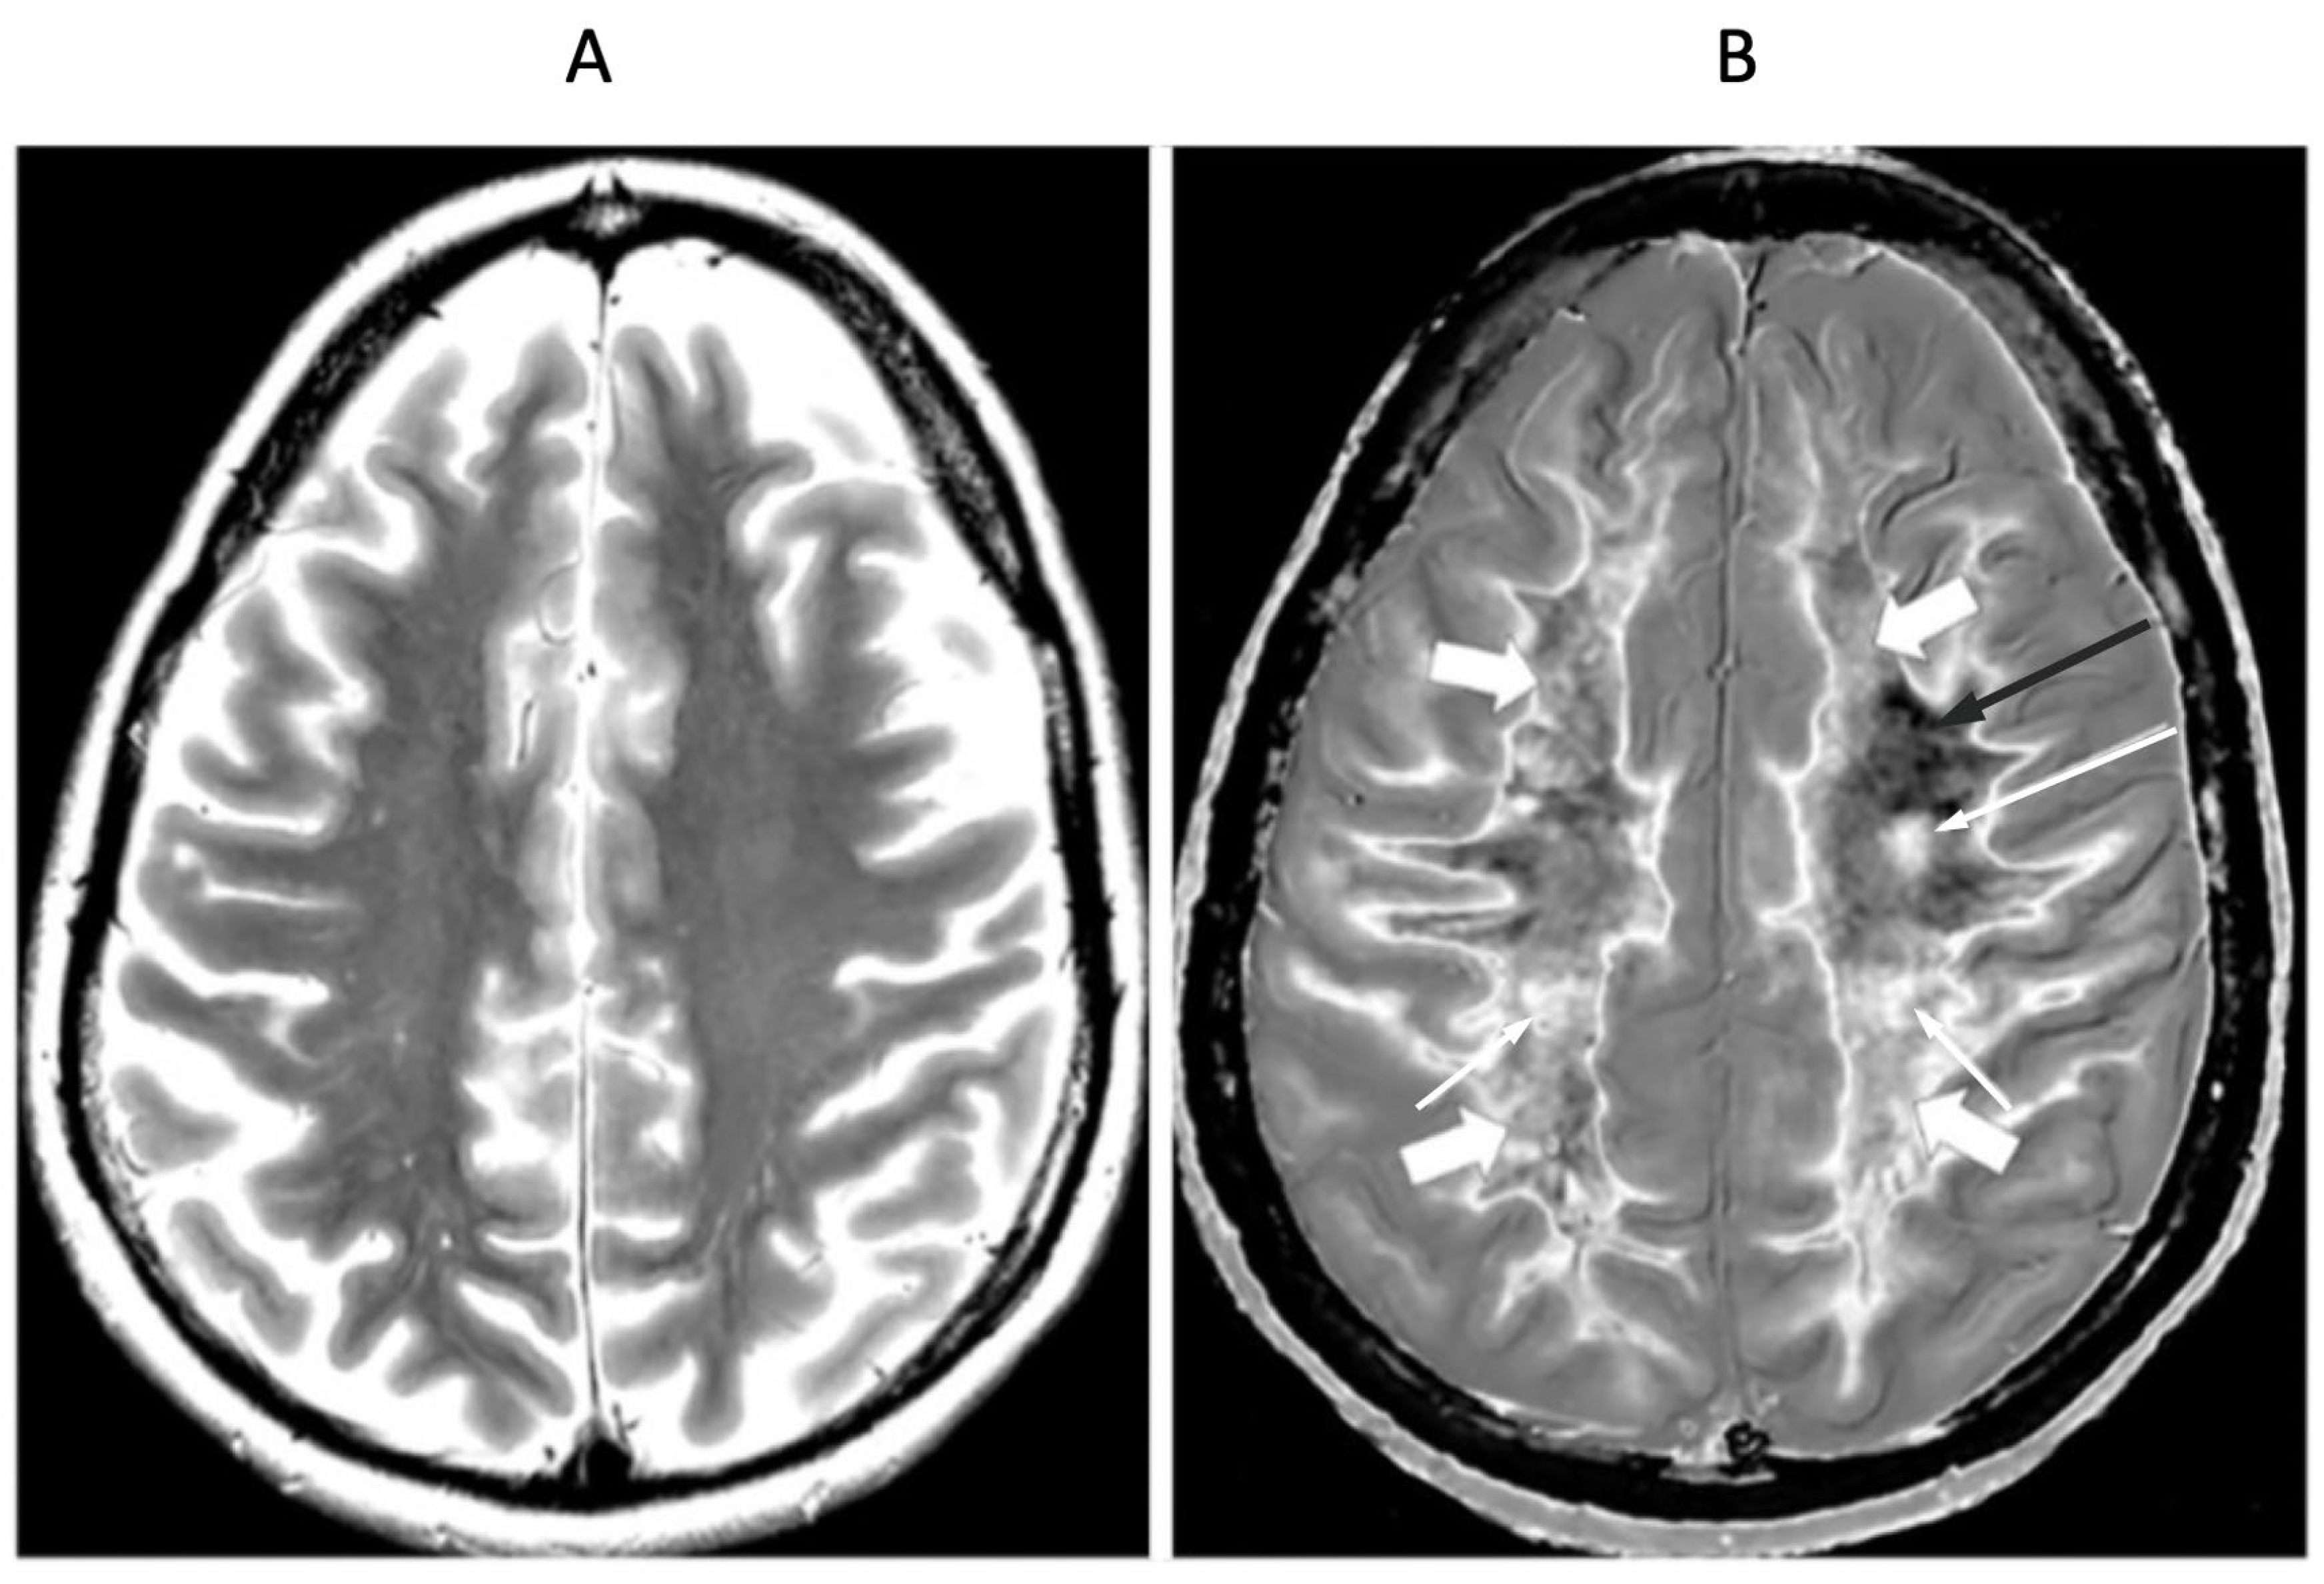

Figure 16.

32-year-old female with MS during a relapse. T

2-FLAIR (A), synthetic narrow mD dSIR (B) and filtered gradient echo (C) images. On the T

2-FLAIR image (A), one lesion is seen (long arrow). The surrounding white matter appears normal. On the dSIR image (B), the lesion shown on the T

2-FLAIR image is seen (long arrow) as well as six other lesions (short arrows). High signal boundaries around lesions are also seen in (B). Some of these lesions show paramagnetic rims on the filtered gradient echo image (arrows) in (C). In addition, most of the white matter in (B) is high signal corresponding to a high grade 4/5 whiteout sign [

1]. The whiteout sign is not seen on the T

2-FLAIR image (A).